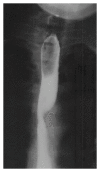

Figure 1

Barium swallow: the characteristic diagonal impression at the level of the third and fourth vertebrae.